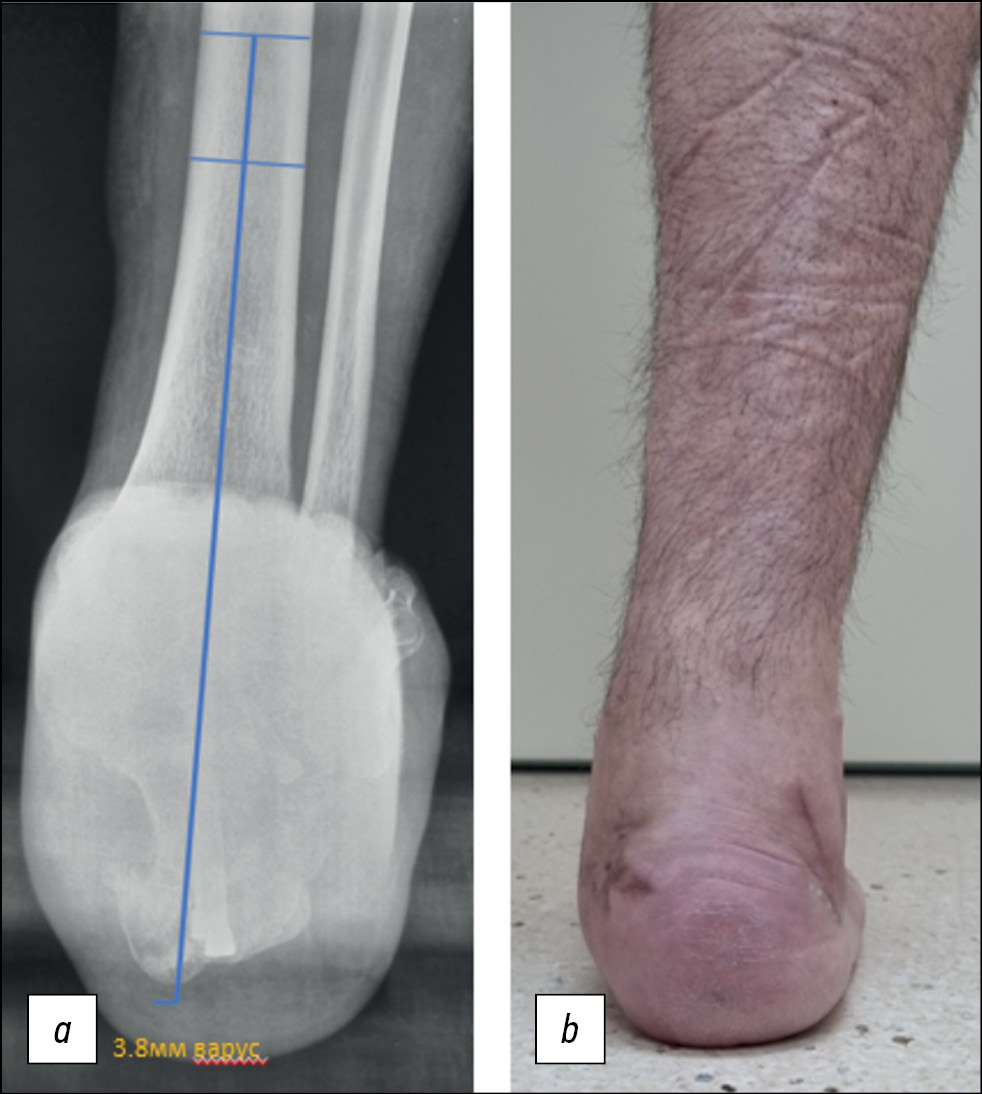

Насколько нам известно, в отечественной литературе до настоящего времени не сообщалось об оптимальном положении пяточной кости после реконструкции её постравматической деформации, и на основании нашего опыта мы с уверенностью можем предостеречь, что важно не путать клинический варус заднего отдела стопы с рентгенологическим варусным отклонением пяточной кости на проекции Зальцмана (рис. 2, a и b).

Таким образом, с клинической точки зрения прямая ось пяточной кости, скорее всего, представляет собой умеренный рентгенологический варус, как показано на рис. 2, b. Именно эта группа пациентов и показала лучшие результаты в настоящем исследовании.

Рис. 2. Послеоперационное (a) рентгенологическое (проекция Зальцмана) и (b) клиническое обследование (положение стоя на оперированной стопе), коррекция деформации с тенденцией на варус 3,8 мм (умеренно-варусное положение) на рентгенологических измерениях. Клинически — ось ближе к нейтральной, без видимого варусного отклонения.

Fig. 2. Postoperative (a) radiographic (Salzman projection) and (b) clinical examination (standing position on the operated foot) deformity correction with a tendency to varus 3.8 mm (moderate-varus position) on radiographic measurements. Clinically, the axis is closer to neutral, without visible varus deviation.

Пациенты, у которых варусное положение заднего отдела стопы определяется клинически, с высокой долей вероятности будут находиться в группе «Варус» при рентгенологическом обследовании, и в нашей работе у них не было зафиксировано аналогичных по значимости положительных результатов. Анализируя проделанную работу, в настоящее время мы стремимся к клинически прямому (нейтральному) положению оси пяточной кости (умеренный рентгенологический варус).